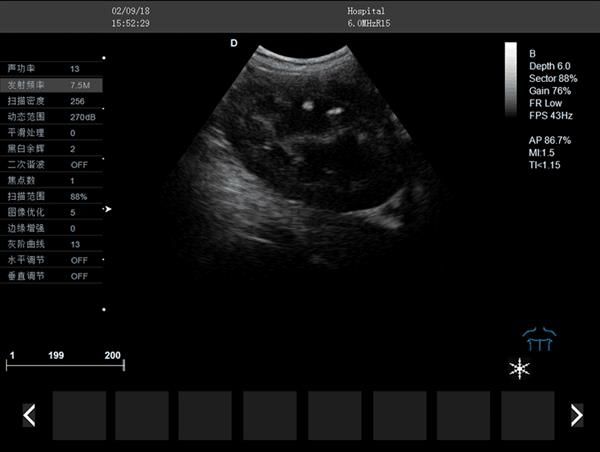

宠物彩色超声诊断仪临床图像: